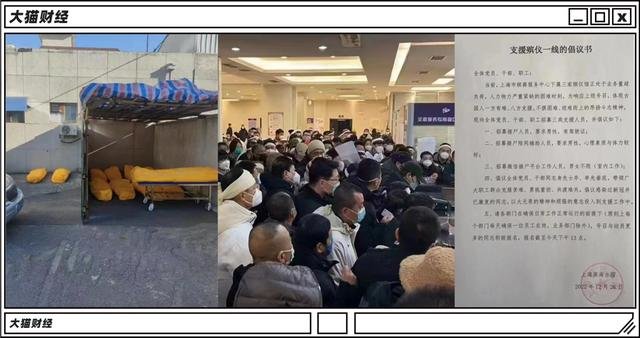

根据一线医生的说法,近期医院的急诊、发热门诊等一直有病人进入,别说ICU了,留观、抢救、输液,各个处室的床位都已经满了,门诊楼的大厅、楼道里面全是人,尤其是以65岁以上的老年人居多。

但是,能有一个坐的地方吸上一口氧,已经算是运气比较好的了,对于突然涌入的感染者,医院似乎也有点措手不及:

1. 急诊不断加床,但是床位明显比人少,有些医院不得不挤占其他科室的床位,根据网友整理的北京近100个二级到三级医院的信息,近日急救床以及留观床的使用率基本在100%,有医院甚至表示,如果入院,最好自己带床;

而在生命的终程,也非常拥挤。

停尸房不够,停车场来替代;殡仪馆拥挤,披麻戴孝都需要排队,急缺人手的殡仪服务中心,已经开始招募党员干部了;而在火葬场,想要早日让家人入土为安,都需要找关系托人了,倒是福寿园、福成股份等殡葬股,已经涨到了3年来的高点。

他同时呼吁,地方能够下基层,让需要住院的患者能够被及时收住院,落实“应收尽收”。

显然,真正的感染高峰还没有真的到来,大城市尚且如此,现在已经开始被波及的中小城市以及县城农村,面对的状况可能就更严峻一些。

压力给到了春节。

返乡潮之后,农村可能还要经历一波比城市更严峻的局部挤兑状况。